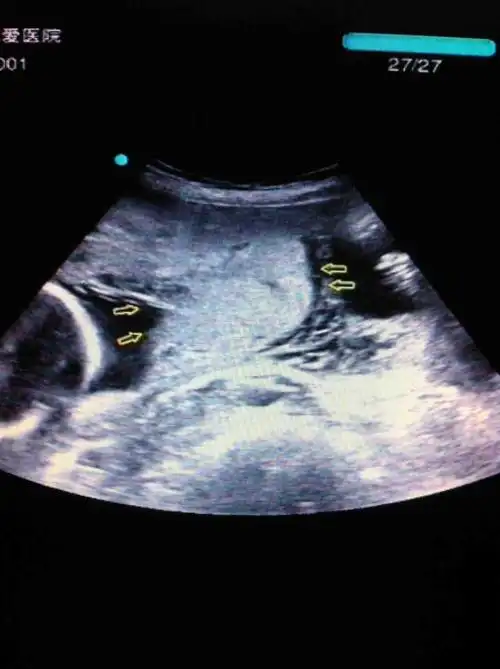

超声所见: 胎儿心率143bmp,胎盘位于子宫前壁,明显增厚,胎盘后方见